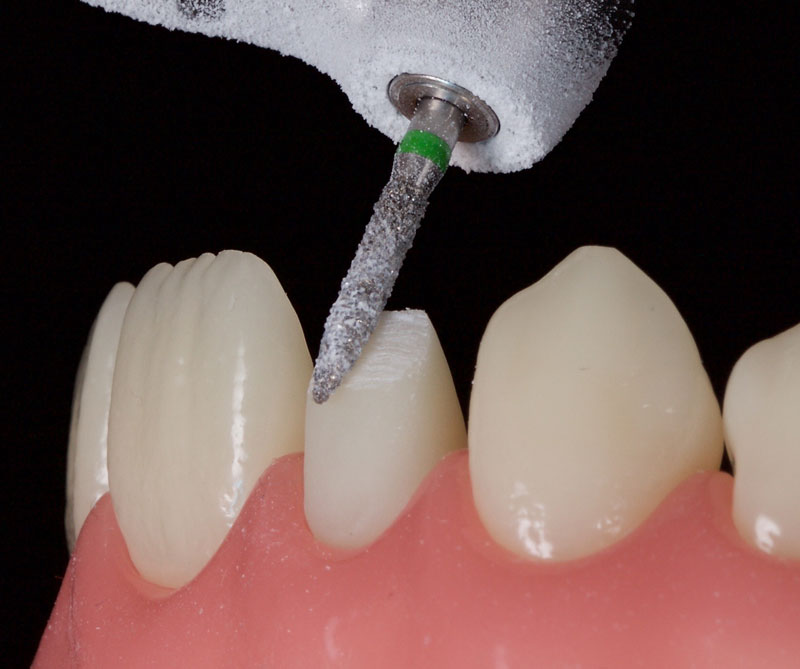

- Minimal tooth preparation/reduction (Fig. 6): This is employed when orthodontics is declined or if the patient already has a Class I incisal relationship with an acceptable overjet and overbite.

This is best achieved by cutting uniform 1.0 mm-deep cuts (dimples or grooves). The tooth is then reduced with a coarse crown diamond, followed by polishing with fine diamonds/discs to smooth the enamel and reduce the risks of white lines due to “enamel peel” (cohesive enamel failure). Typically, only the incisal-facial half must be reduced, leaving the gingiva untouched.